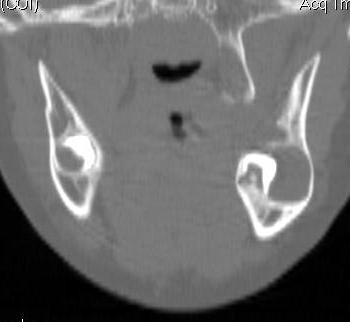

Cyst Associated with an Impacted Tooth in a Child